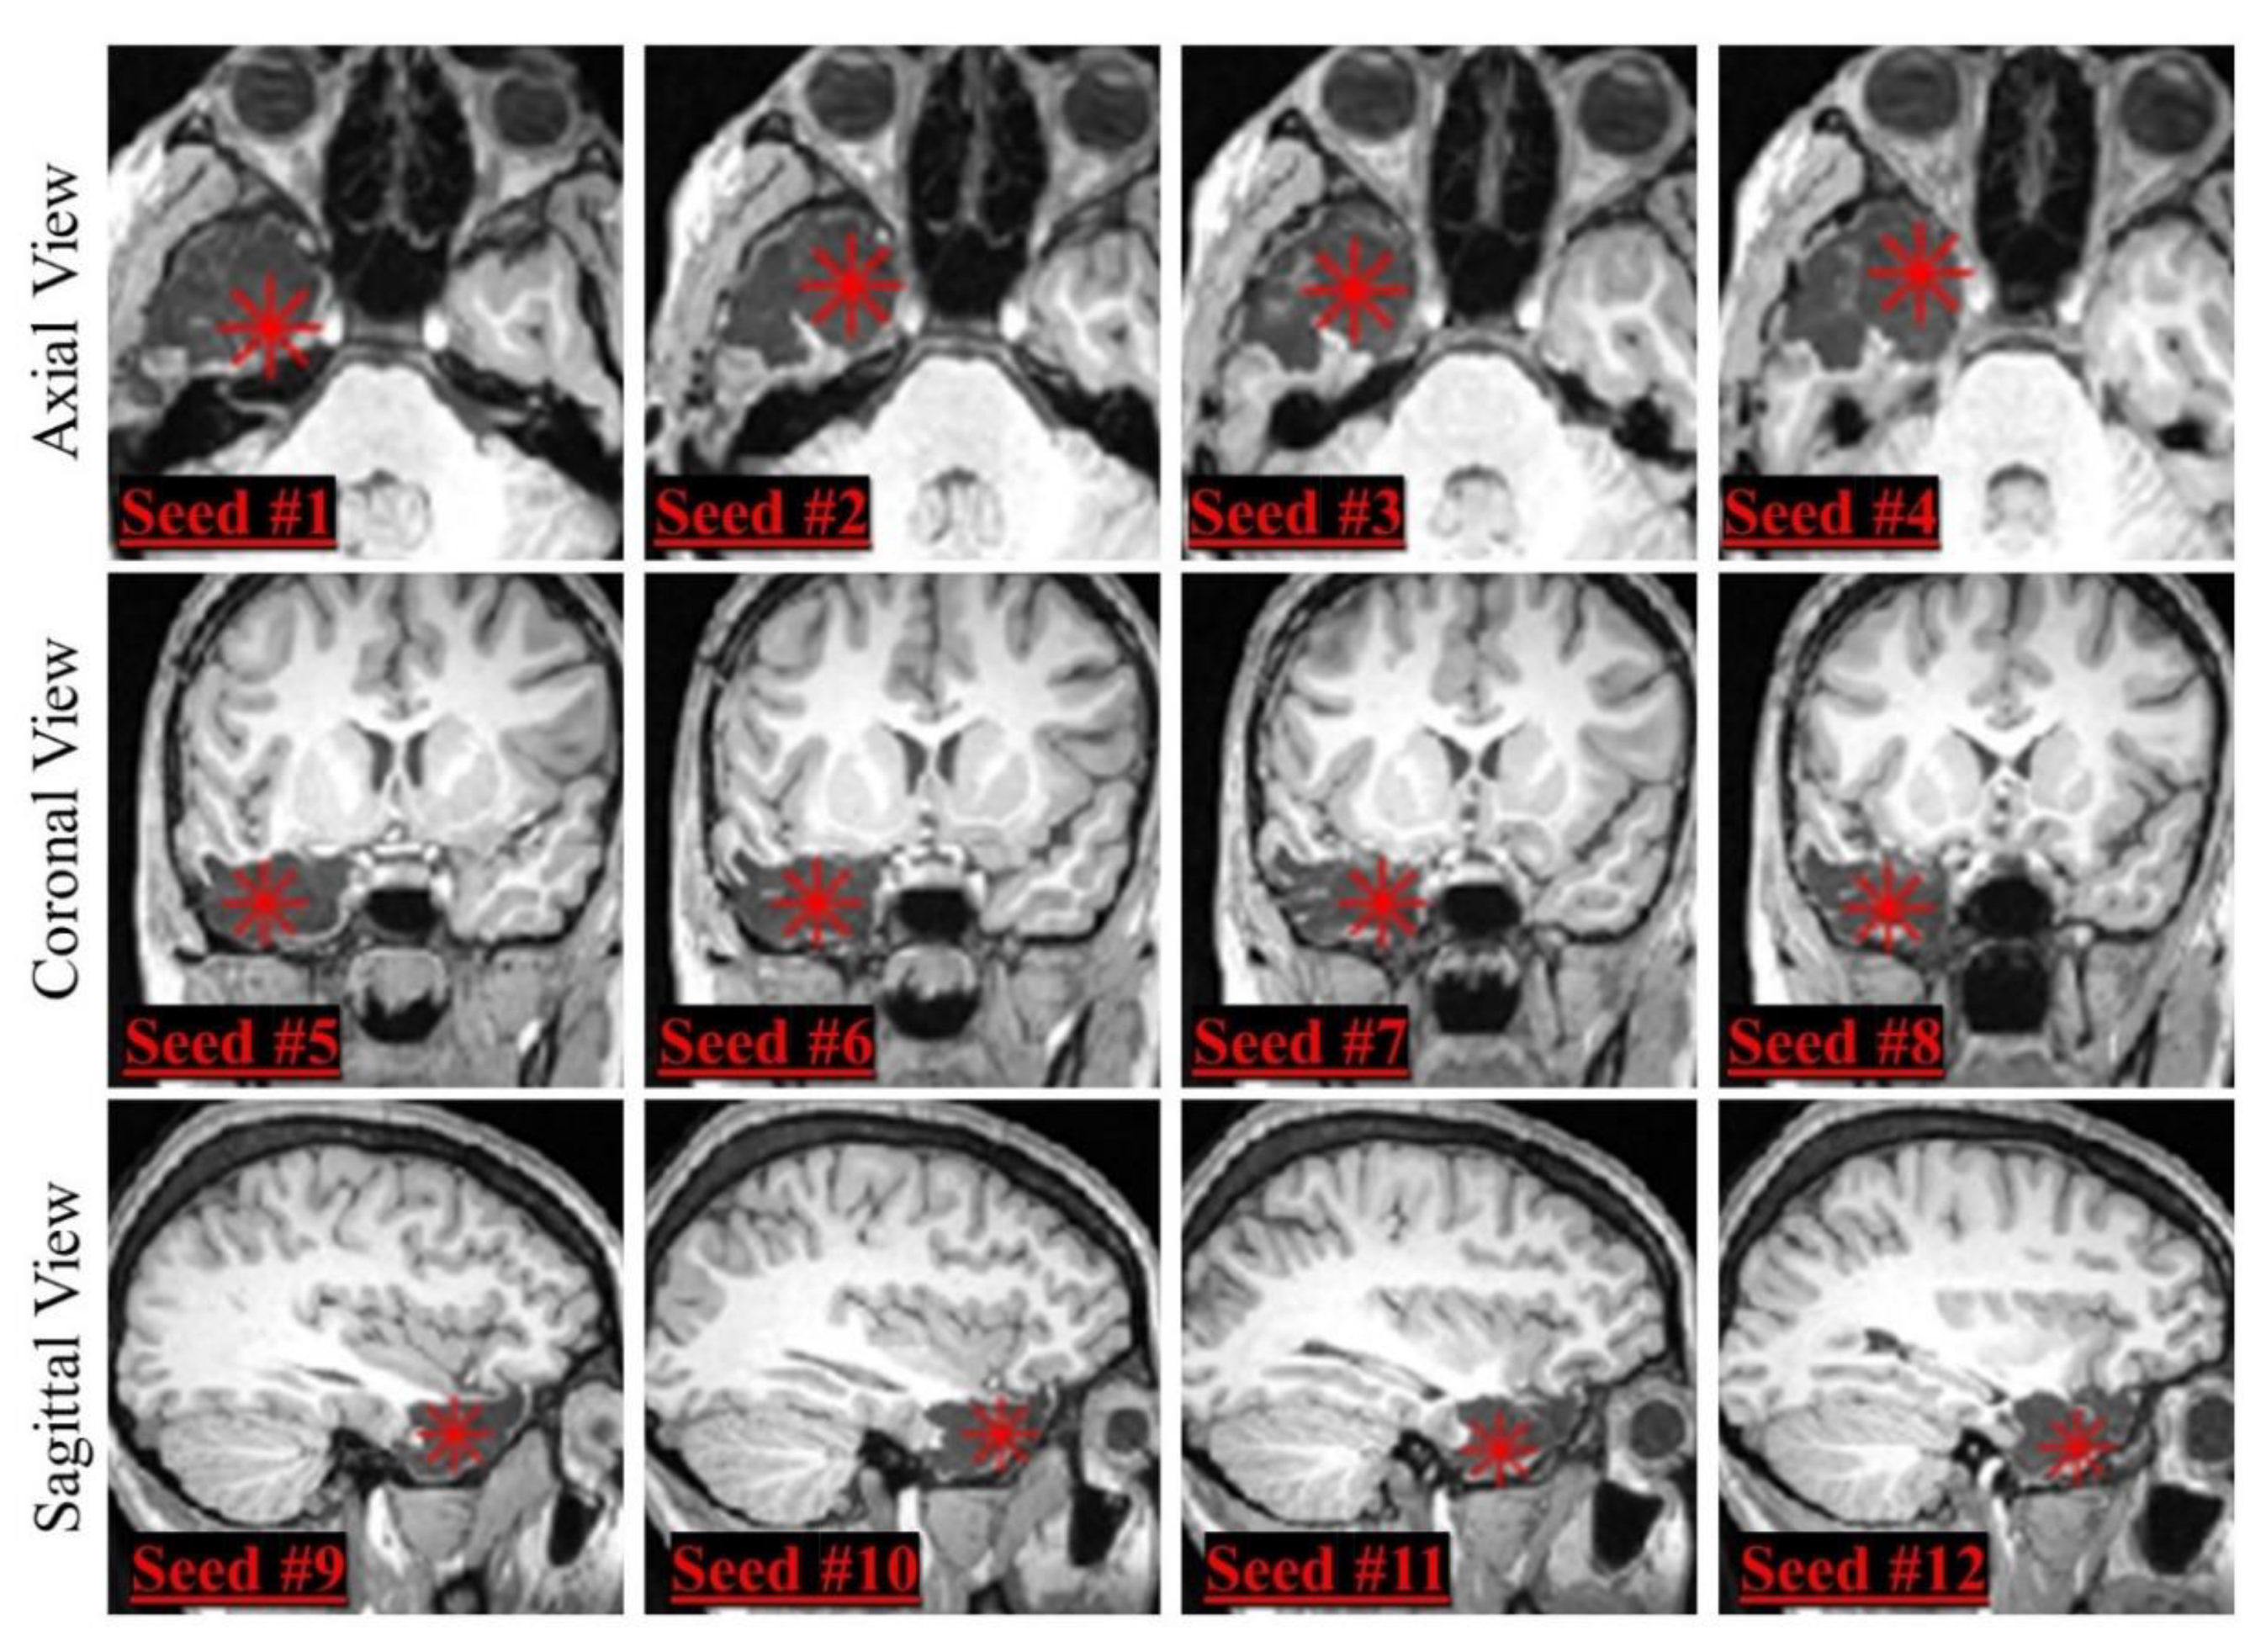

2.2. Region-Growing Algorithm

3.4. Single-Parameter Tuning